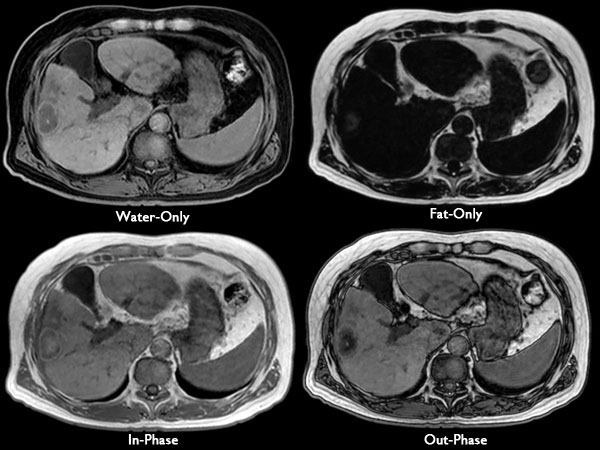

Axial mDIXON